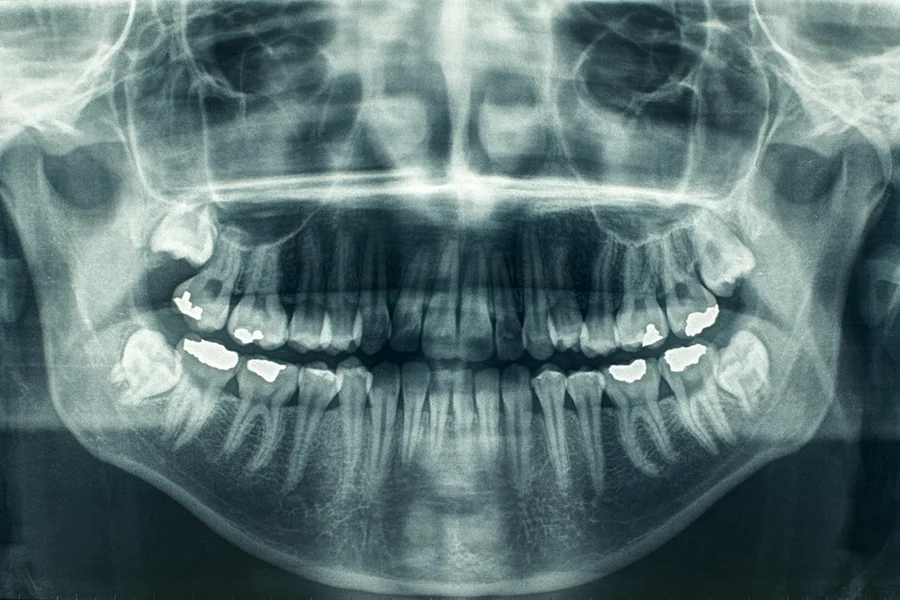

Dental X-rays reveal what the eye cannot see. They help in spotting decay between teeth, identify bone loss, and detect infections at the root of the tooth. X-rays are crucial for planning treatments like braces or implants. The process is quick, usually taking only a few minutes. The technology used is safe, emitting low levels of radiation. According to the U.S. Food and Drug Administration, the benefits of these X-rays far outweigh the risks, especially when protective measures are in place.

| Panoramic | Provides a broad view of the jaws, teeth, sinuses, and joints. |

Bitewing X-rays are common during check-ups. They help find decay between teeth. Periapical X-rays focus on a few teeth, giving detailed views. Panoramic X-rays are wide, capturing the entire mouth, and are helpful for complex procedures. Each has a specific purpose and benefits your dental health in different ways.